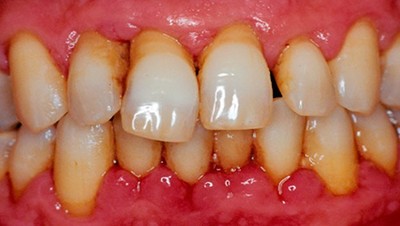

Фото 1. Острый локальный пародонтит. Воспалены десны в области двух зубов, наблюдается покраснение и кровотечение.

Фото 2. Локальный пародонтит. Воспалены несколько зубов, в области воспаления наблюдается кровотечение.